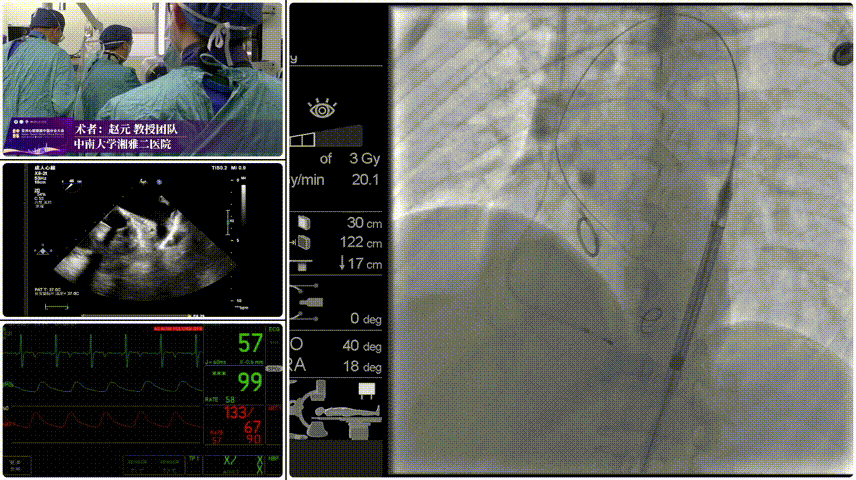

Step 4.稳定脱钩无位移。

Step 5.最终造影:位置合适,瓣膜形态良好,无瓣周漏。

患者压差由105mmHg降至17mmHg。

该环上瓣采用独特的平衡收腰结构,在适配极小瓣环的同时,实现了锚定稳定性与血流动力学的双重优化。针对患者极小瓣环的特点,选择AV23规格瓣膜。术后超声显示,患者跨瓣压差由术前105mmHg 骤降至17mmHg,血流动力学显著改善,无瓣周漏。

手术过程与术后转归